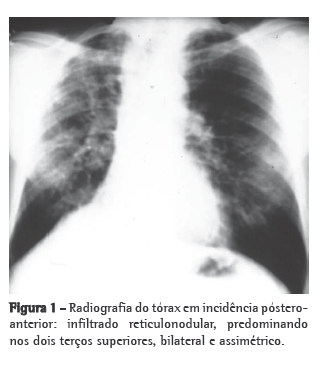

Na radiografia simples de tórax (Figura 1), pode ser visualizado infiltrado reticulonodular, predominante nos dois terços superiores de ambos os pulmões, assimétrico, com hipertransparência junto às bases pulmonares.(1,2,4)